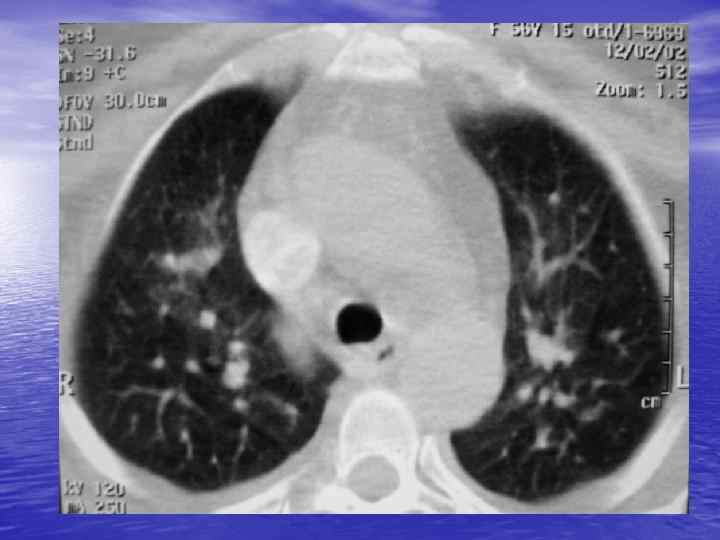

Преимущества спиральной КТ: ü Возможность проведения исследования с болюсным ü ü ü ü ü контрастированием Высокая разрешающая способность; Высокая скорость исследования; Получение высококачественных изображений костных структур; Возможность обследования всего тела; Возможность проведения исследования больных под наркозом; Возможность детальной оценки состояния крупных и периферических сосудов в условиях искусственного контрастирования; Высокая информативность метода при черепномозговых травмах в остром периоде; Ранняя диагностика ишемических и геморрагических инсультов; Метод выбора для диагностики заболеваний легких; Планирование лучевой терапии.